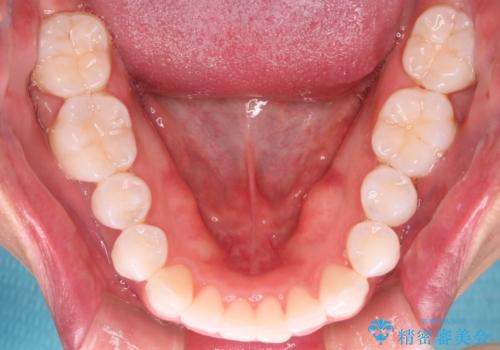

治療について

治療当初は、計画通りに治療が進むか心配でしたが、しっかりマウスピースを使用していただいたことで

治療期間も長引くことなく歯並びを綺麗に改善することが出来ました。

患者様の希望もあり、前歯の微調整で1回リファイメント(マウスピースの再発注)を行いました。

患者様の希望に沿う治療を提案することができ良かったと思います。